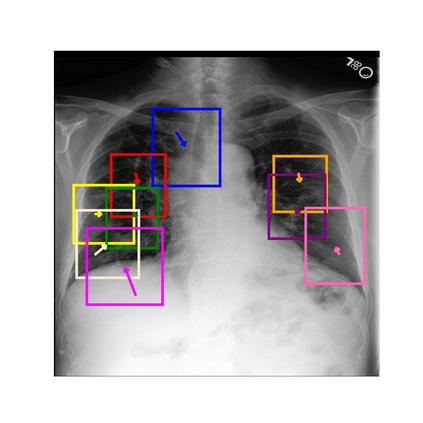

To address these issues, we propose a novel Adaptive patch-word Matching (AdaMatch) model to correlate chest X-ray (CXR) image regions with words in medical reports and apply it to CXR-report generation to provide explainability for the generation process. AdaMatch exploits the fine-grained relation between adaptive patches and words to provide explanations of specific image regions with corresponding words. To capture the abnormal regions of varying sizes and positions, we introduce the Adaptive Patch extraction (AdaPatch) module to acquire the adaptive patches for these regions adaptively. In order to provide explicit explainability for CXR-report generation task, we propose an AdaMatch-based bidirectional large language model for Cyclic CXR-report generation (AdaMatch-Cyclic). It employs the AdaMatch to obtain the keywords for CXR images and `keypatches' for medical reports as hints to guide CXR-report generation. Extensive experiments on two publicly available CXR datasets prove the effectiveness of our method and its superior performance to existing methods.